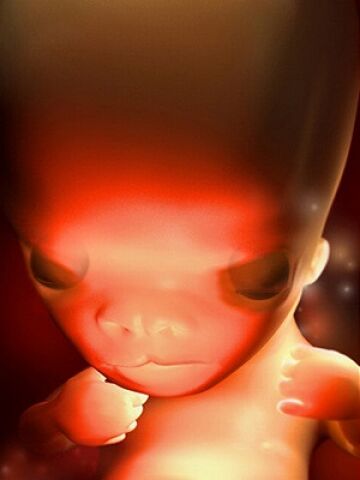

第8周的胚胎大约有16毫米长,看上去像颗葡萄。胚胎的器官已经开始有明显的特征,手指和脚趾间看上去有少量的蹼状物。这时胚胎像跳动的豆子一样开始有运动。因为骨髓还没有成形,现在由肝脏来生产大量的红细胞,直到骨髓成形后去接管肝脏的作用。

胚胎的器官特征开始明显,各个不同的器官开始忙碌地发育。从现在开始到20周,你的胎儿将迅速成长,并且在几个星期内就会有明显的轮廓,这个时期的成长速度就像孕早期心脏和大脑的发育时期一样。现在各种复杂的器官都开始成长,牙和腭开始发育,耳朵也在继续成形,胎儿的皮肤像纸一样薄,血管清晰可见。